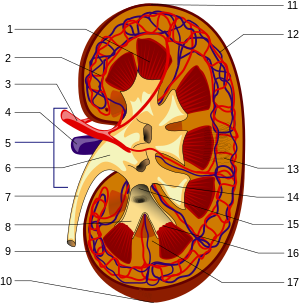

The kidneys are 11 centimeters long paired reddish brown organs situated on the posterior wall of the abdominal cavity one on each side of the vertebral column and capped by the adrenal gland. H ions are produced as a natural byproduct of the metabolism of dietary proteins and accumulate in the blood over time. Connective tissue anchors the kidneys to surrounding structures and helps maintain their normal position.

Upper portions of the kidneys are somewhat protected by the eleventh and twelfth ribs figure 1. Anatomy of the kidneys. Each kidney weighs about 125175 g in males and 115155 g in females.

Due to the presence of the liver the right kidney is slightly lower than the left kidney. They are about 1114 cm in length 6 cm wide and 4 cm thick and are directly covered by a fibrous capsule composed of dense. Anatomy of the urinary system.

The kidneys monitor and regulate the levels of hydrogen ions h and bicarbonate ions in the blood to control blood ph. Glomerular filtration glomerular filtration is the renal process whereby fluid in the blood is filtered across the capillaries of the glomerulus. The right kidney is lower than the left due to displacement by the liver.

Location of the kidneys there are two kidneys which lie retroperioneally in the lumbar area. The angiotensinconverting enzyme converts angiotensin i to angiotensin ii which stimulates the adrenal cortex to secrete aldosterone a hormone that is involved in increasing blood pressure. The basic anatomy and physiology of the kidney how kidney function changes through life the anatomy of the kidney the kidneys are comple x and beautiful organs.